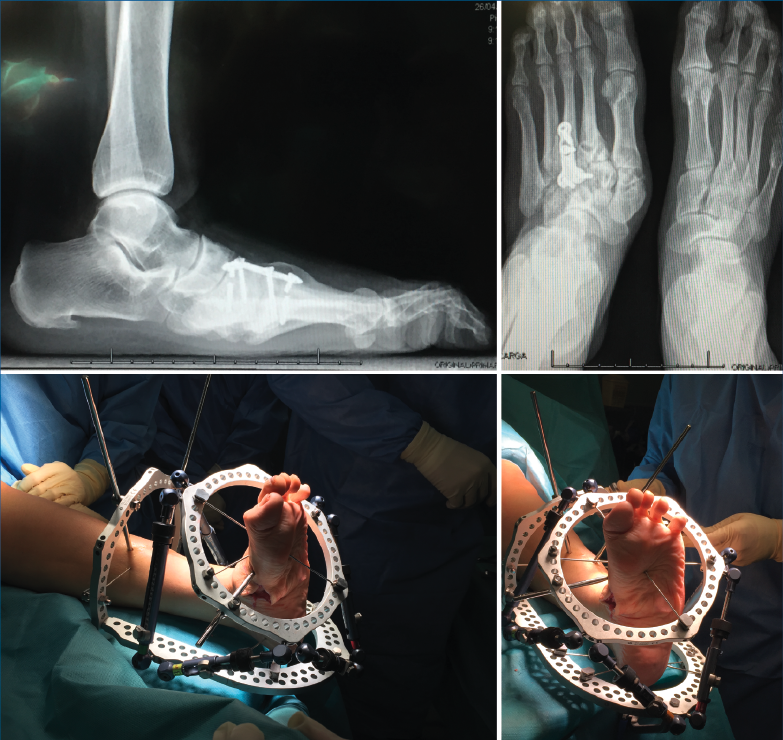

Figura 3. Corrección de deformidades y fijación externa con sistema TSF®.

- Cirugía de pie diabético (fijación circular): corrección de deformidades y fijación externa con sistema TSF®(Figura 3).